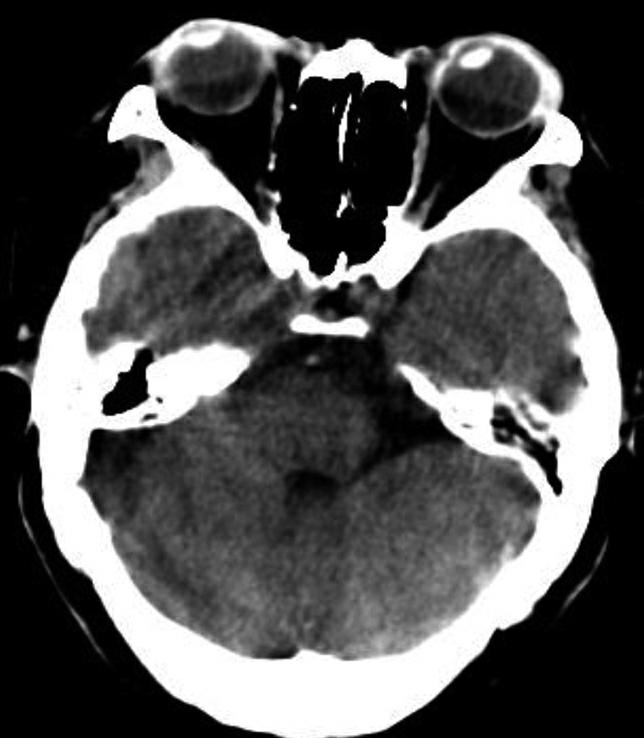

蝶鞍两侧为海绵窦,其内包含颈内动脉及第Ⅲ~Ⅵ对脑神经。海绵窦的密度升高或体积增大常提示病变存在。海绵窦外侧为颞叶,两者之间隔以海绵窦外侧壁。鞍背后方为桥前池及其后方的脑桥,桥前池内可见基底动脉断面,呈圆形稍高密度影。层面中部两侧为颞骨乳突部,其内气化的骨性腔隙为乳突气房。脑桥后方为第四脑室,呈半圆形或新月形,小脑半球的病变(如肿瘤、炎症、出血等)常压迫第四脑室,导致其变形甚至闭塞(图1-2-13)。两侧小脑半球间为小脑蚓部。小脑半球与颞骨乳突部间可见乙状窦。小脑蚓部后方为直窦与上矢状窦汇入窦汇处,窦汇两侧为横窦。静脉窦血栓时可见上述静脉窦增宽、密度明显升高(图1-2-14)。

图1-2-13 第四脑室变形(小脑转移瘤)

A.第四脑室受压变形右移(白箭),提示左侧小脑半球病变;B.左侧小脑半球环形强化结节(黑箭),为瘤体,其周围伴有低密度水肿区